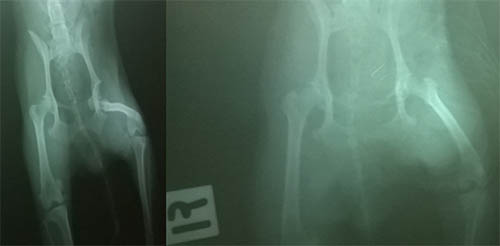

进行推拿后几小时,该犬就可以行走;2天后可以正常行走;1个月后恢复,正常活动。X线片显示髋关节已复位(见图2)。

图2:治疗前后髋关节X线照片